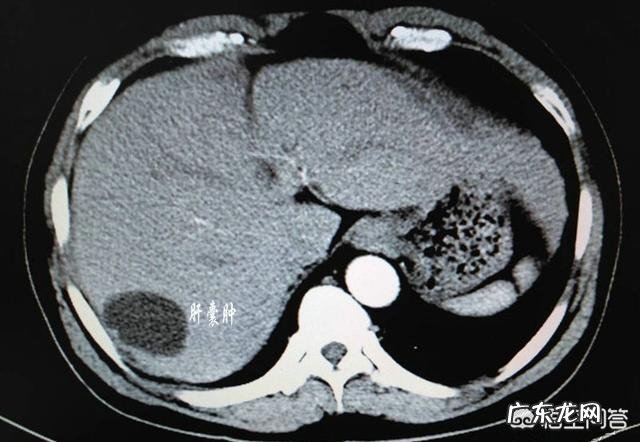

现在很多人在体检时 , 会偶然发现自己有肝囊肿 , 当发现了肝囊肿 , 有些人会比较迷惑 , 有些人会比较害怕 。肝囊肿到底是什么疾病 , 与肝癌会有什么关系么?

肝囊肿是较为常见的肝脏良性疾病 , 是长在肝脏组织内的“水泡” , 水泡内部充满液体 , 外面则是包围着简单的表皮细胞 , 很像一个水球 。肝囊肿可以为单发 , 也可以是多发 。主要分为寄生虫性和非寄生虫性肝囊肿 。后者更为常见 , 又可分为先天性、创伤性、炎症性和肿瘤性囊肿 。临床又以先天性肝囊肿最为多见 , 占90%以上 。而胆道炎症、肝脏损伤等也会引起肝囊肿 。

此外 , 单发性肝囊肿以20-50岁女性多见 , 囊肿发生于肝右叶居多 , 小者直径仅数毫米 , 大者可占据整个肝脏 。多发性肝囊肿以40-60岁女性多见 , 囊肿大小不等 , 多累及全肝 , 肝脏可增大变形 , 但也可局限于一段或一叶 , 囊液澄清透明 , 多不含胆汁 。

几乎每天看CT片子都能看到肝囊肿 , 肝囊肿是比较常见的肝的良性病变 , 尤其是先天性肝囊肿是临床比较常见的囊肿的类型 , 除此之外还有炎症性、创伤性肝囊肿 。